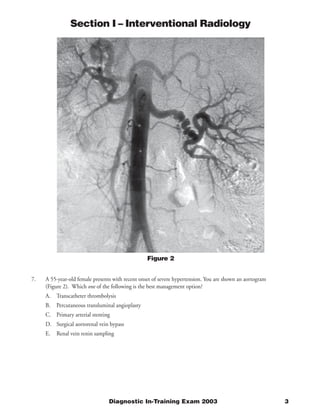

The document describes a case involving a chest x-ray and pulmonary angiogram findings in a 57-year-old female patient who presented with chest pain two weeks following a hemorrhagic stroke. The pulmonary angiogram shows multiple filling defects in the left main pulmonary artery and its branches, consistent with pulmonary embolism. While anticoagulation is usually the standard therapy for pulmonary embolism, it is contraindicated in this patient due to her recent stroke. Therefore, the best management option is placement of an inferior vena cava filter to prevent further pulmonary emboli while existing clots dissolve, as anticoagulation cannot be used due to her recent hemorrhagic stroke.